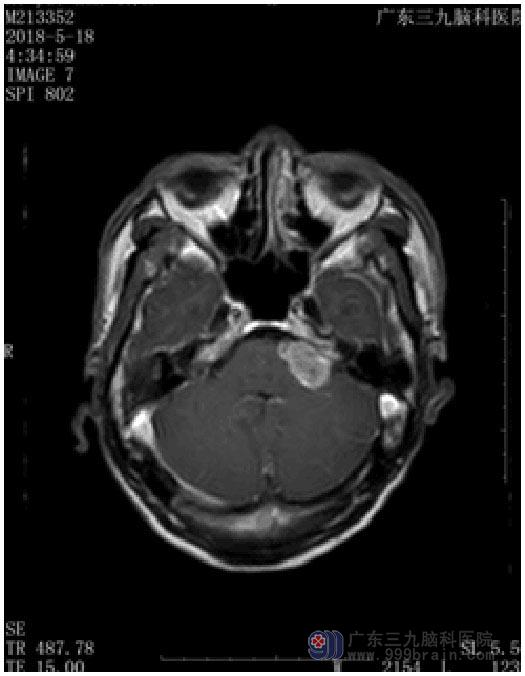

几个月前出现头晕,以为自己长时间低头工作,颈椎有问题,在医院多次针灸、按摩等治疗。直到一次晕倒后,被送去当地医院行CT检查,才发现是“左侧桥小脑角占位”。广东三九脑科医院进一步头颅MRI检查,提示:左侧桥小脑角区占位性病变,考虑听神经鞘瘤可能性大,病灶大小约2.6cm×2.7cm×2.3cm。